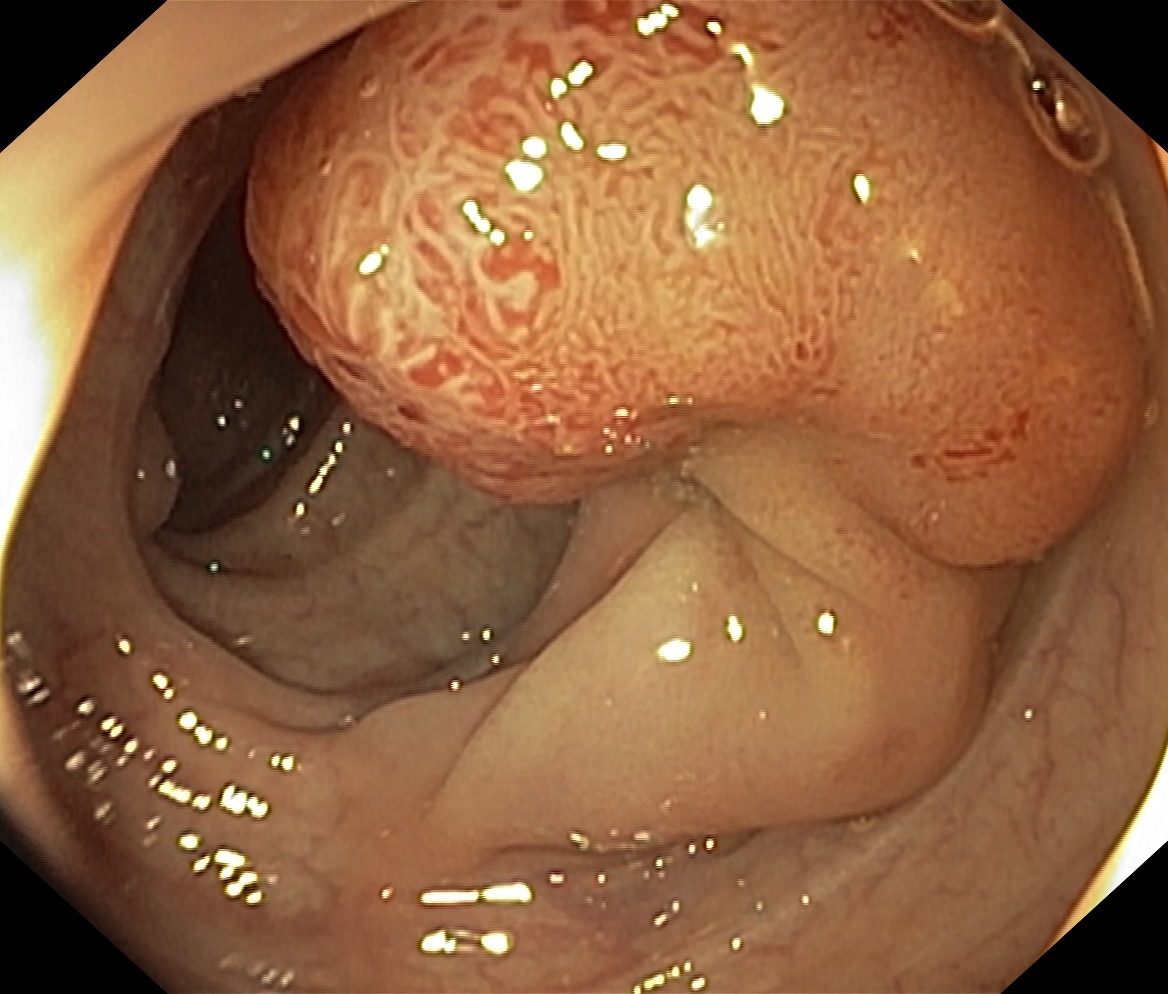

Polipy